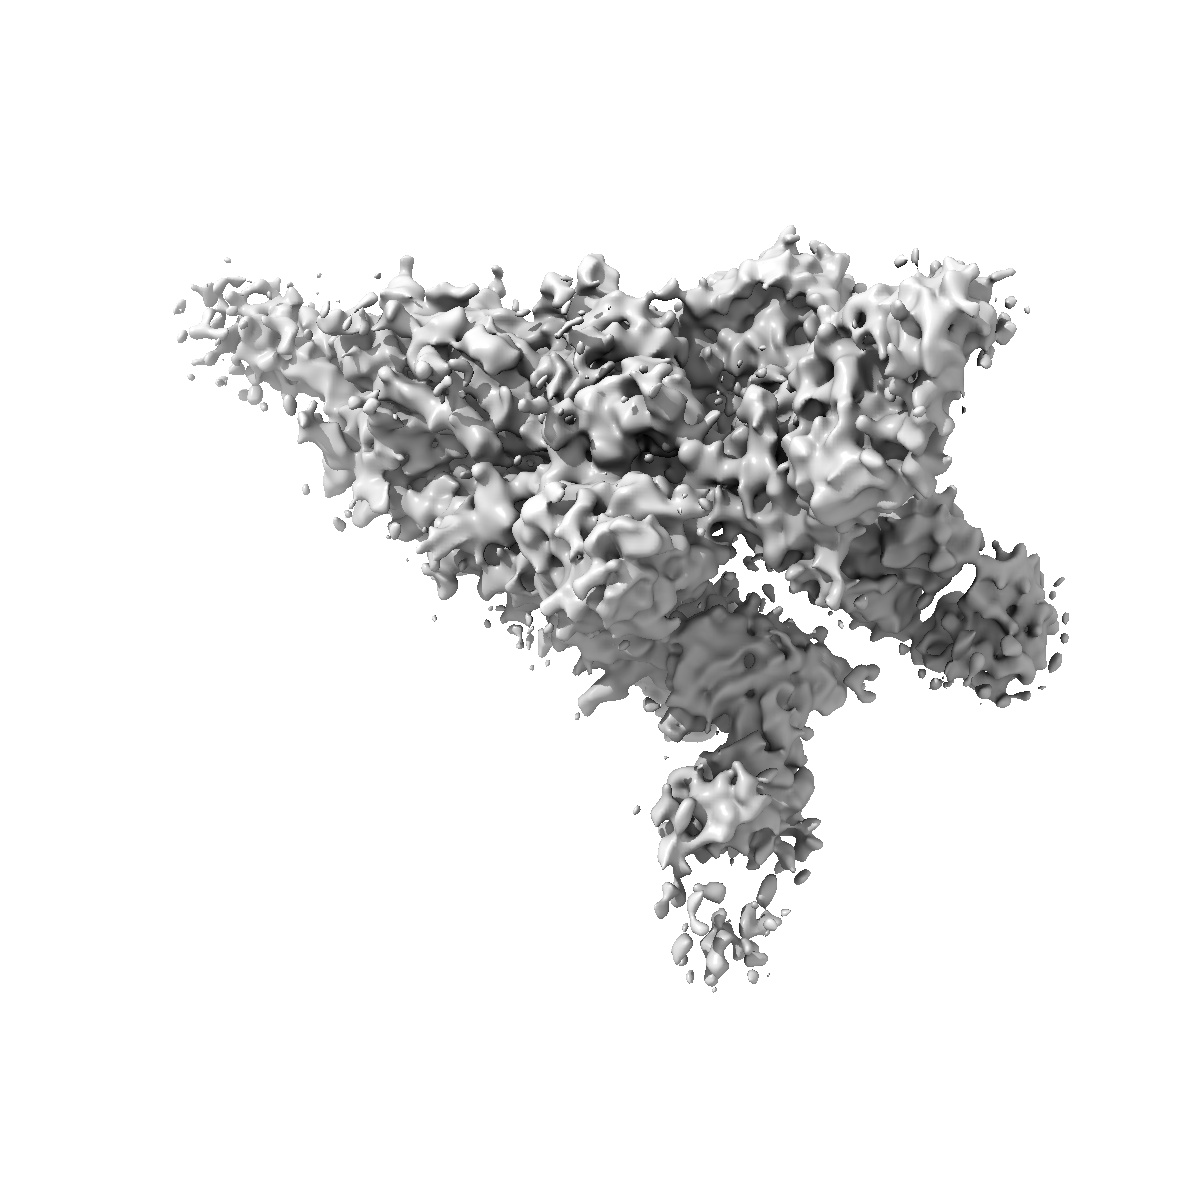

Spike 3-up RBD with THSC20.HVTR04 (Fab4): State - III

Single-particle4.9 Å

Sample: Wuhan SARS-CoV-2 Spike trimer complex with THSC20.HVTR04 (Fab4) [State III - 3-up RBD]

Cryo-EM reveals conformational variability in the SARS-CoV-2 spike protein RBD induced by two broadly neutralizing monoclonal antibodies.

(2025) Rsc Adv , 15 , 14385 - 14399